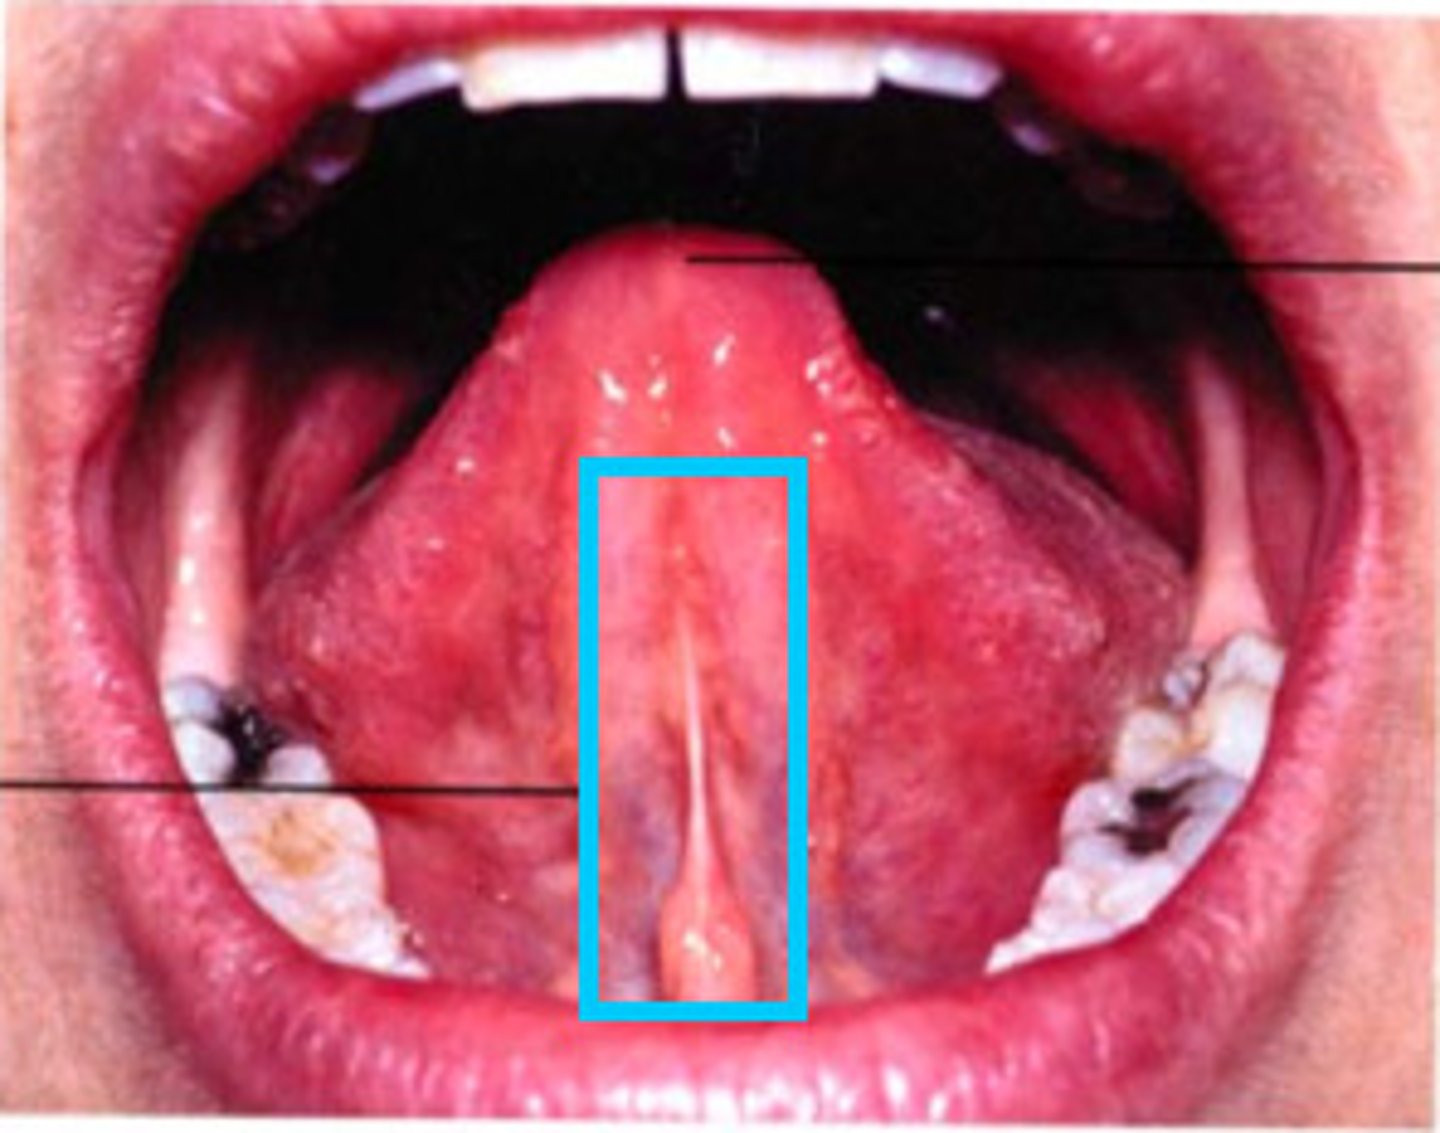

Oral vestibule

Gingival sulcus

Lingual frenum

Epiglottis

H

Esophagus

F

Hard palate

A

Laryngopharynx

G

Lingual tonsil

J

Oropharynx

I

Palatine tonsil

K

Soft palate

M

Tongue

E

Uvula

L